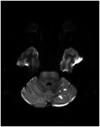

In this review article, we summarized the current advances in rescue management for reperfusion therapy of acute ischemic stroke from large vessel occlusion due to underlying intracranial atherosclerotic stenosis (ICAS). It is estimated that 24-47% of patients with acute vertebrobasilar artery occlusion have underlying ICAS and superimposed in situ thrombosis. These patients have been found to have longer procedure times, lower recanalization rates, higher rates of reocclusion and lower rates of favorable outcomes than patients with embolic occlusion. Here, we discuss the most recent literature regarding the use of glycoprotein IIb/IIIa inhibitors, angioplasty alone, or angioplasty with stenting for rescue therapy in the setting of failed recanalization or instant/imminent reocclusion during thrombectomy. We also present a case of rescue therapy post intravenous tPA and thrombectomy with intra-arterial tirofiban and balloon angioplasty followed by oral dual antiplatelet therapy in a patient with dominant vertebral artery occlusion due to ICAS. Based on the available literature data, we conclude that glycoprotein IIb/IIIa is a reasonably safe and effective rescue therapy for patients who have had a failed thrombectomy or have residual severe intracranial stenosis. Balloon angioplasty and/or stenting may be helpful as a rescue treatment for patients who have had a failed thrombectomy or are at risk of reocclusion. The effectiveness of immediate stenting for residual stenosis after successful thrombectomy is still uncertain. Rescue therapy does not appear to increase the risk of sICH. Randomized controlled trials are warranted to prove the efficacy of rescue therapy.